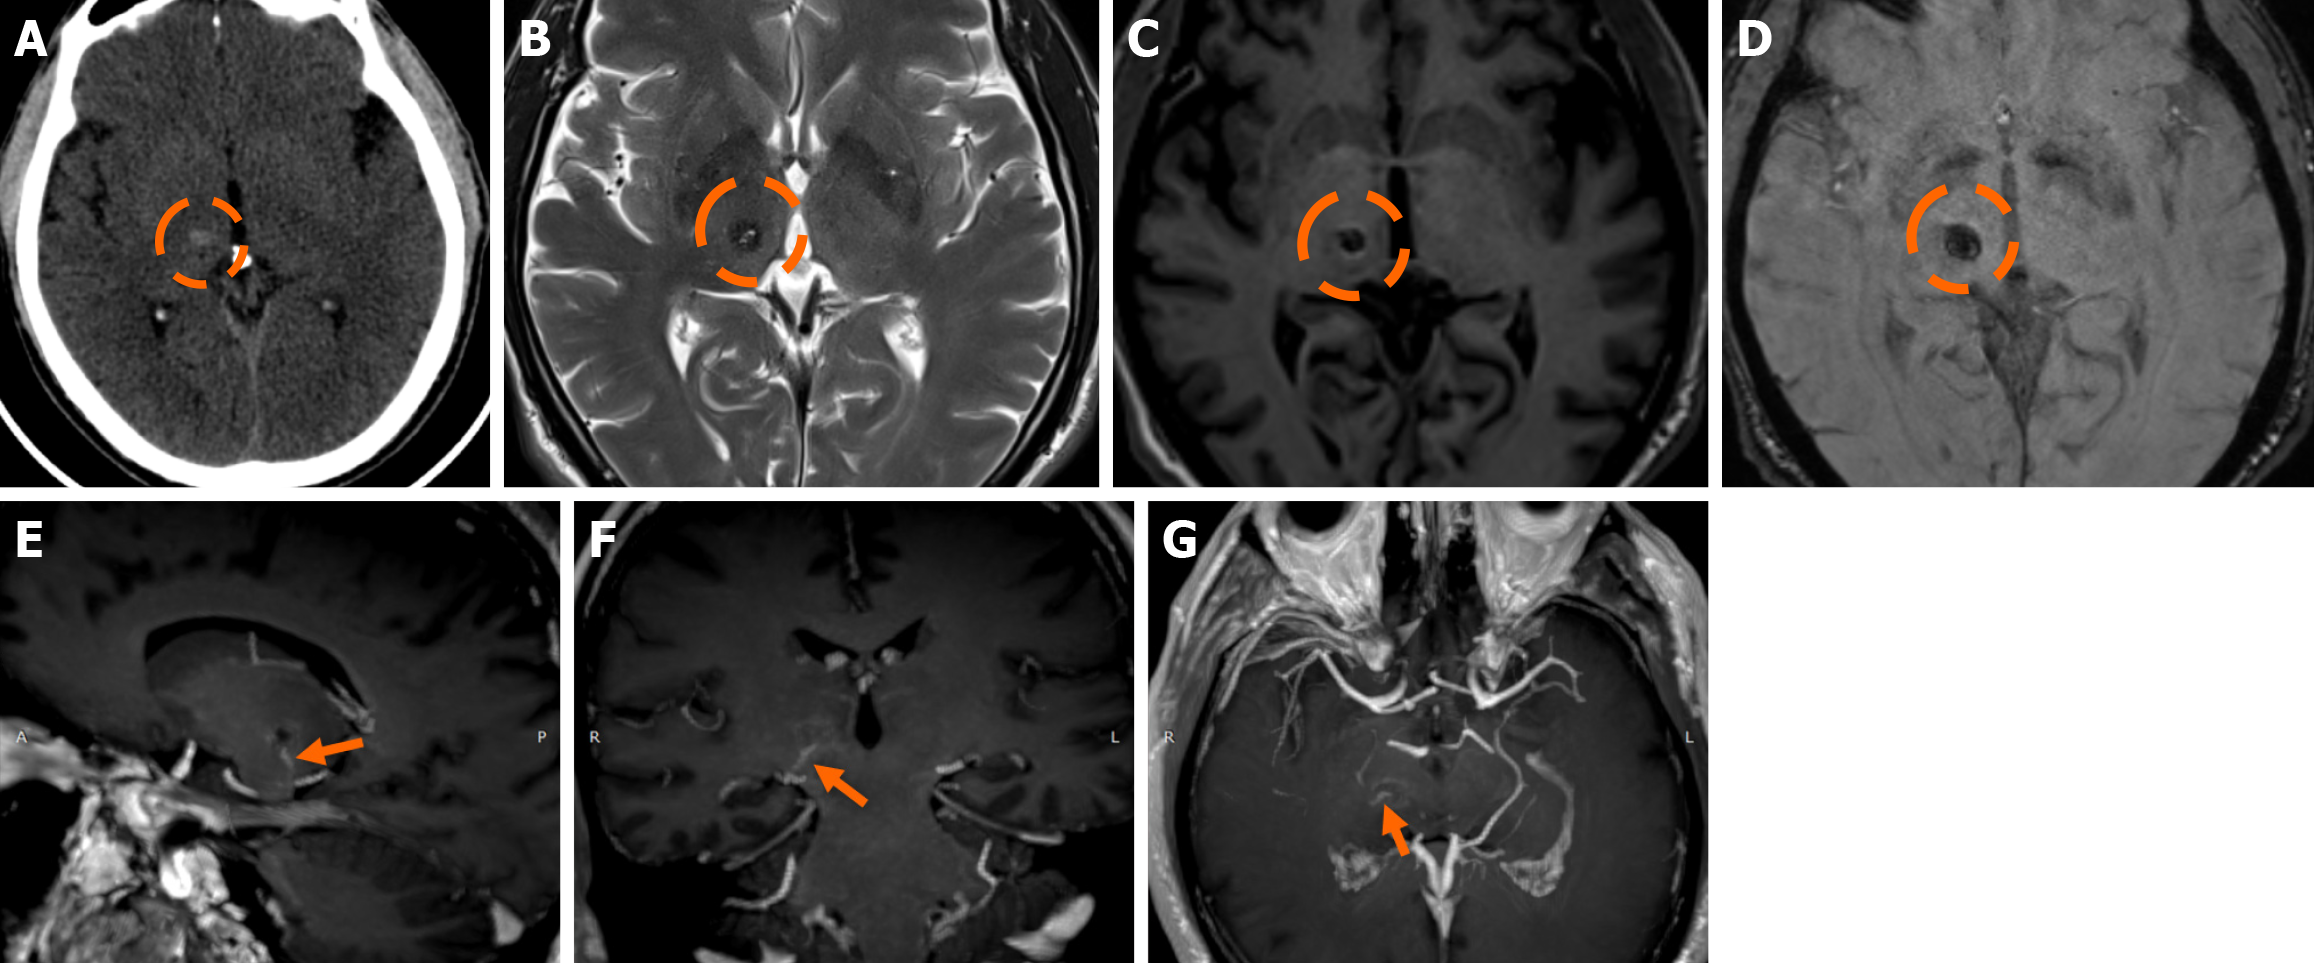

Functional MRI (fMRI) depends on blood oxygen level-dependent contrast, and changes are attributed to both extravascular tissue and local capillaries and veins. Theoretically, DVAs can contribute to the fMRI signal and can potentially lead to pseudoactivations during presurgical mapping[58]. Various examples of DVAs on CTs and MRIs are shown in Figures 1 and 2.

The clinical applicability of the Zabramski classification is still being investigated. A retrospective cohort study evaluating the imaging evolution and clinical trajectory of 255 untreated patients with sporadic CMs over a follow-up period of approximately five years provided evidence that the Zabramski classification may facilitate risk stratification and contribute to treatment planning, particularly in determining the necessity for surgical intervention[89]. Furthermore, a recent study by Saari et al[88] established an association between the radiological characteristics of the Zabramski classification and their clinical relevance, emphasizing that type I lesions have a higher likelihood of becoming symptomatic. Nikoubashman et al[90] suggested an additional category (type V lesions) accounting for cavernomas presenting with gross extralesional hemorrhage. Various examples of CMs on CTs and MRIs, including familial cerebral CM cases, are shown in Figures 4, 5 and 6.

Imaging findings in coexistent DVAs and CMs will be the combination of those described for each malformation separately. Awareness of the possibility of their coexistence may prove invaluable in clinical practice. This is because recognition of a DVA close to a brain hemorrhage may raise suspicion for an underlying CM as the most likely etiology. Additional examinations and follow-up imaging following hematoma resolution will further enhance diagnostic confidence. Figures 8, 9, 10 and 11 illustrate clinical examples in which identifying the synchronous presence of a DVA adjacent to a brain hemorrhage (or suspected brain hemorrhage) enabled the diagnosis of a probable underlying CM as the most likely etiology, thereby avoiding unnecessary examinations or interventions.